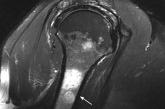

58-year-old man • bilateral shoulder pain • history of prostate cancer • limited shoulder range of motion • Dx?

► Bilateral shoulder pain

► History of prostate cancer

► Limited shoulder range of motion